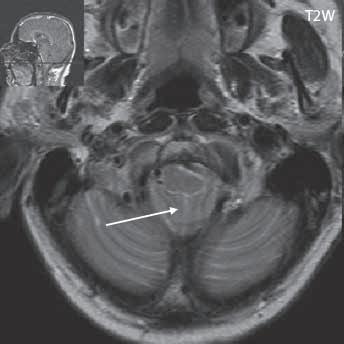

I.1.7 Chiariho malformace (ArnoldovaChiariho malformace)

Rozlišujeme tři formy (typy) této malformace. Chiari I je charakterizován sestoupením mozečkových tonzil do foramen okcipitale magnum do oblasti krční páteře (u dospělých jsou tonzily mozečku max. 5 mm pod úrovní baze lební, u malých dětí (do 10 roků) do 6 mm. Tonzily bývají na podélném řezu přirovnávány ke klínům, které jako by byly zatlučeny do týlního otvoru „pek like“. Chiari II malformace je ve 100 % doprovázena otevřeným spinálním dysrafismem (obvykle myelomeningokélou). Chiari III lze definovat jako Chiari II + okcipitální nebo cervikální encefalomeningokéla. Chiari IV, kde je navíc přítomna hypoplazie mozečku, do této skupiny nezařazujeme, vývojově patří do poruch ventrální indukce.

Zobrazení

Chiari I: CT a MR zobrazí malou zadní jámu lební, absenci cisteren zadní jámy lební, pokles tonzil, krátký a konkávní klivus, poruchu cirkulace mozkomíšního moku v oblasti foramen magnum a následný hydrocefalus. MR navíc může prokázat edém krční míchy a ve vysokém procentu případů hydrosyringomyelii.

Chiari II: CT a MR zobrazí malou zadní jámu lební, absenci nebo výraznou redukci cisterny cerebelomedulární a dalších kmenových cisteren, konkávní klivus. Mohou být abnormality v oblasti foramen okcipitale magnum, nízký úpon tentoria, někdy absence nebo fenestrace falx cerebri. MR lépe ukáže kaudálně uloženou a protáhlou IV. komoru (někdy je přirovnávána až ke stéblu slámy), protažený pons a další možné, přidružené abnormality (hydrosyringomyelii, agenezi, hypogenezi nebo fenestraci corpus callosum…).

Obr. I.1.7a Sestup mozečkových tonzil (šipka), Chiariho malformace I

Obr. I.1.7b Sestup mozečkových tonzil, „pek like“ (šipka), Chiariho malformace I c d